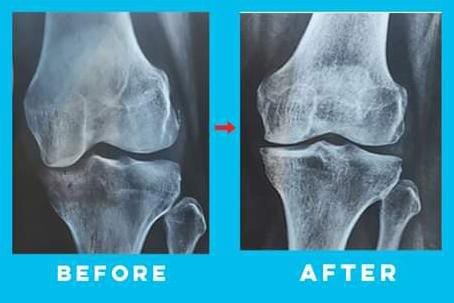

Don't Replace, Regrow...

Don't Replace the knee, Rebuild the Cartilage....

Corrects the gap in the knee

At we understand the impact that gaps or misalignments in the knee can have on your comfort and mobility. Our dedicated team of experts is here to offer a specialized knee therapy program designed to close the gap and restore optimal joint alignment.